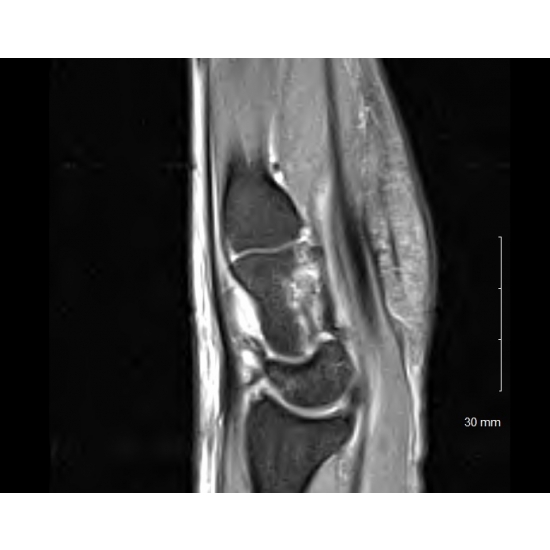

The initial, x-rays revealed a non-displaced radial styloid fracture Case Photo #1 . The patient was placed in a short-arm fracture brace. She continued to participate in soccer activities without restrictions. Her radial wrist pain improved within 3 days, but the swelling and pain over the mid-dorsal aspect of the wrist persisted. Due to persistent pain and swelling, the patient was referred for an MRI of her wrist Case Photo #2 .

The patient's case and MRI imaging was reviewed with an orthopedic surgeon. MRI demonstrated a comminuted fracture of the capitate and non-displaced radial styloid fracture Case Photo #2 , Case Photo #3 , Case Photo #4 , Case Photo #5 , Case Photo #6 . She was transitioned into a short-arm thumb-spica splint.